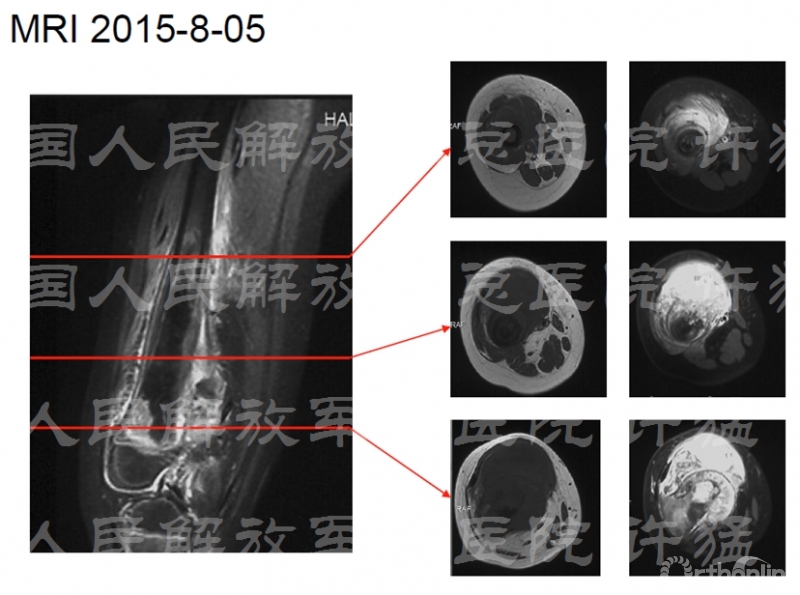

入院前检查:

核磁显示股四头肌伸膝装置受到肿瘤累及